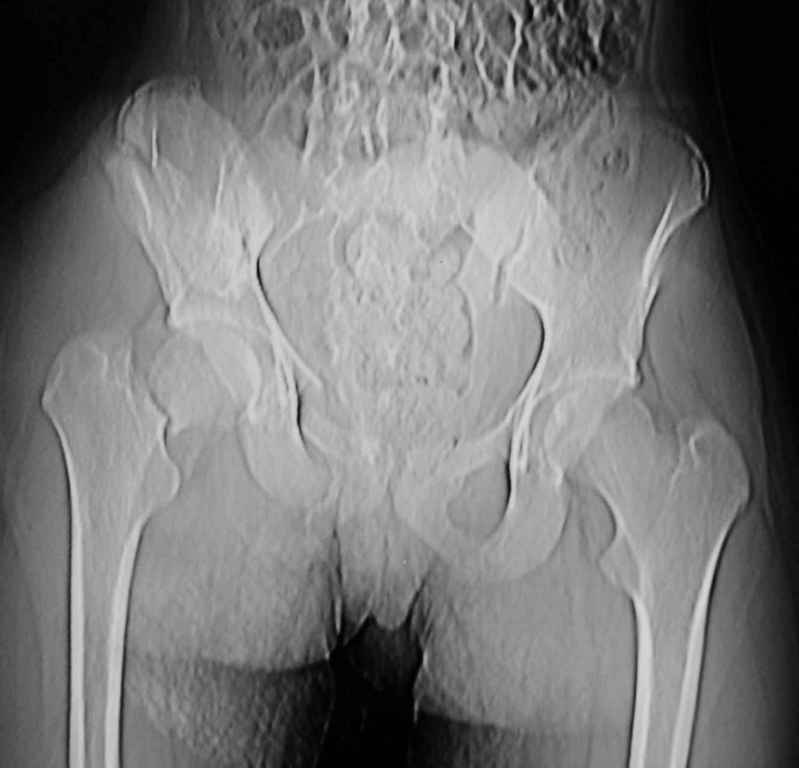

Ребенок 13 лет Перелом костей таза.

Уважаемые коллеги, в нашу клинику поступил ребенок 13 лет; травма четыре дня назад(падение с 5-го этажа). Помогите определиться с дальнейшей тактикой.